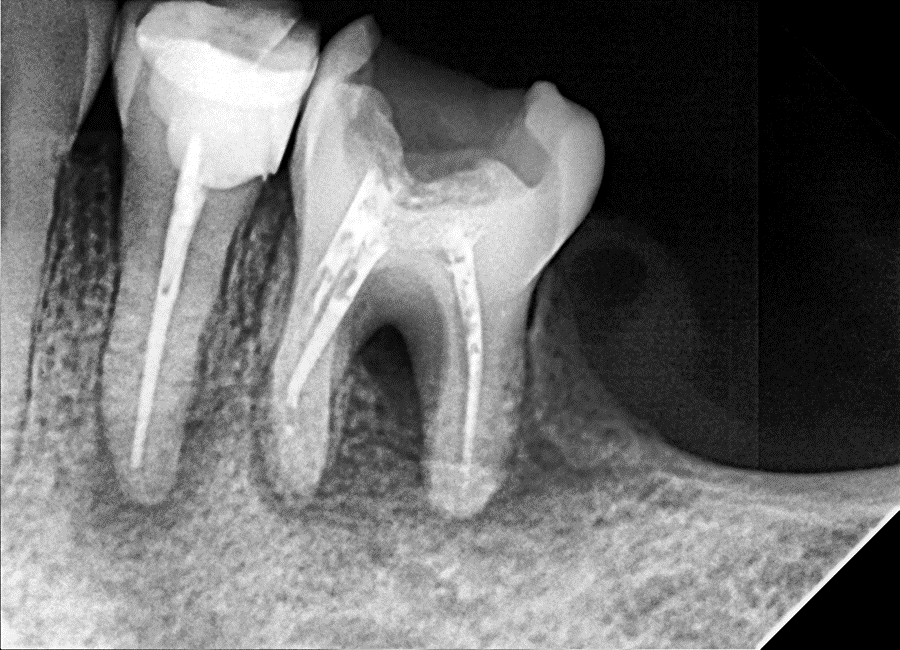

Figure 1. Pre-operative radiograph of tooth #36 showing extensive periapical radiolucency and complete loss of bone in the furcation area.

Radiographic Findings:

Large periapical radiolucency with Noticed  bone loss in the furcation area .